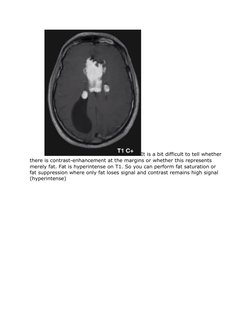

T1-weighted (lipoma)

It is a bit difficult to tell whether

there is contrast-enhancement at the margins or whether this represents

merely fat. Fat is hyperintense on T1. So you can perform fat saturation or

fat suppression where only fat loses signal and contrast remains high signal

(hyperintense)